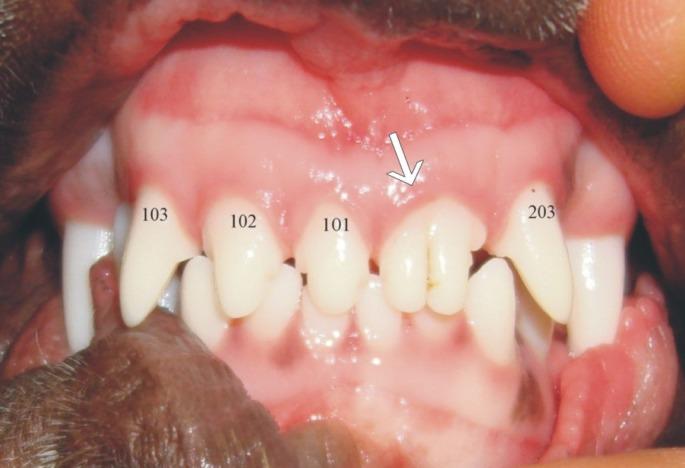

Developmental Structural Tooth Defects in Dogs - Experience From Veterinary Dental Referral Practice and Review of the Literature.

Developmental tooth abnormalities in dogs are uncommon in general veterinary practice but understanding thereof is important for optimal management in order to maintain masticatory function through preservation of the dentition. The purpose of this review is to discuss clinical abnormalities of the enamel and general anatomy of dog teeth encountered in veterinary dental referral practice and described in the literature. More than 900 referral cases are seen annually between the two referral practices. The basis of the pathogenesis, resultant clinical appearance, and the principles of management for each anomaly will be described. Future research should be aimed toward a more detailed analysis of these conditions so rarely described in the literature.